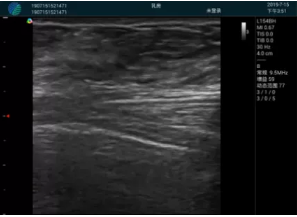

可視化穿刺引導(dǎo)

M20實(shí)時(shí)引導(dǎo):向包塊后方間隙注射利多卡因

清晰顯示腺體內(nèi)低回聲快影,邊界清晰,包膜較光滑